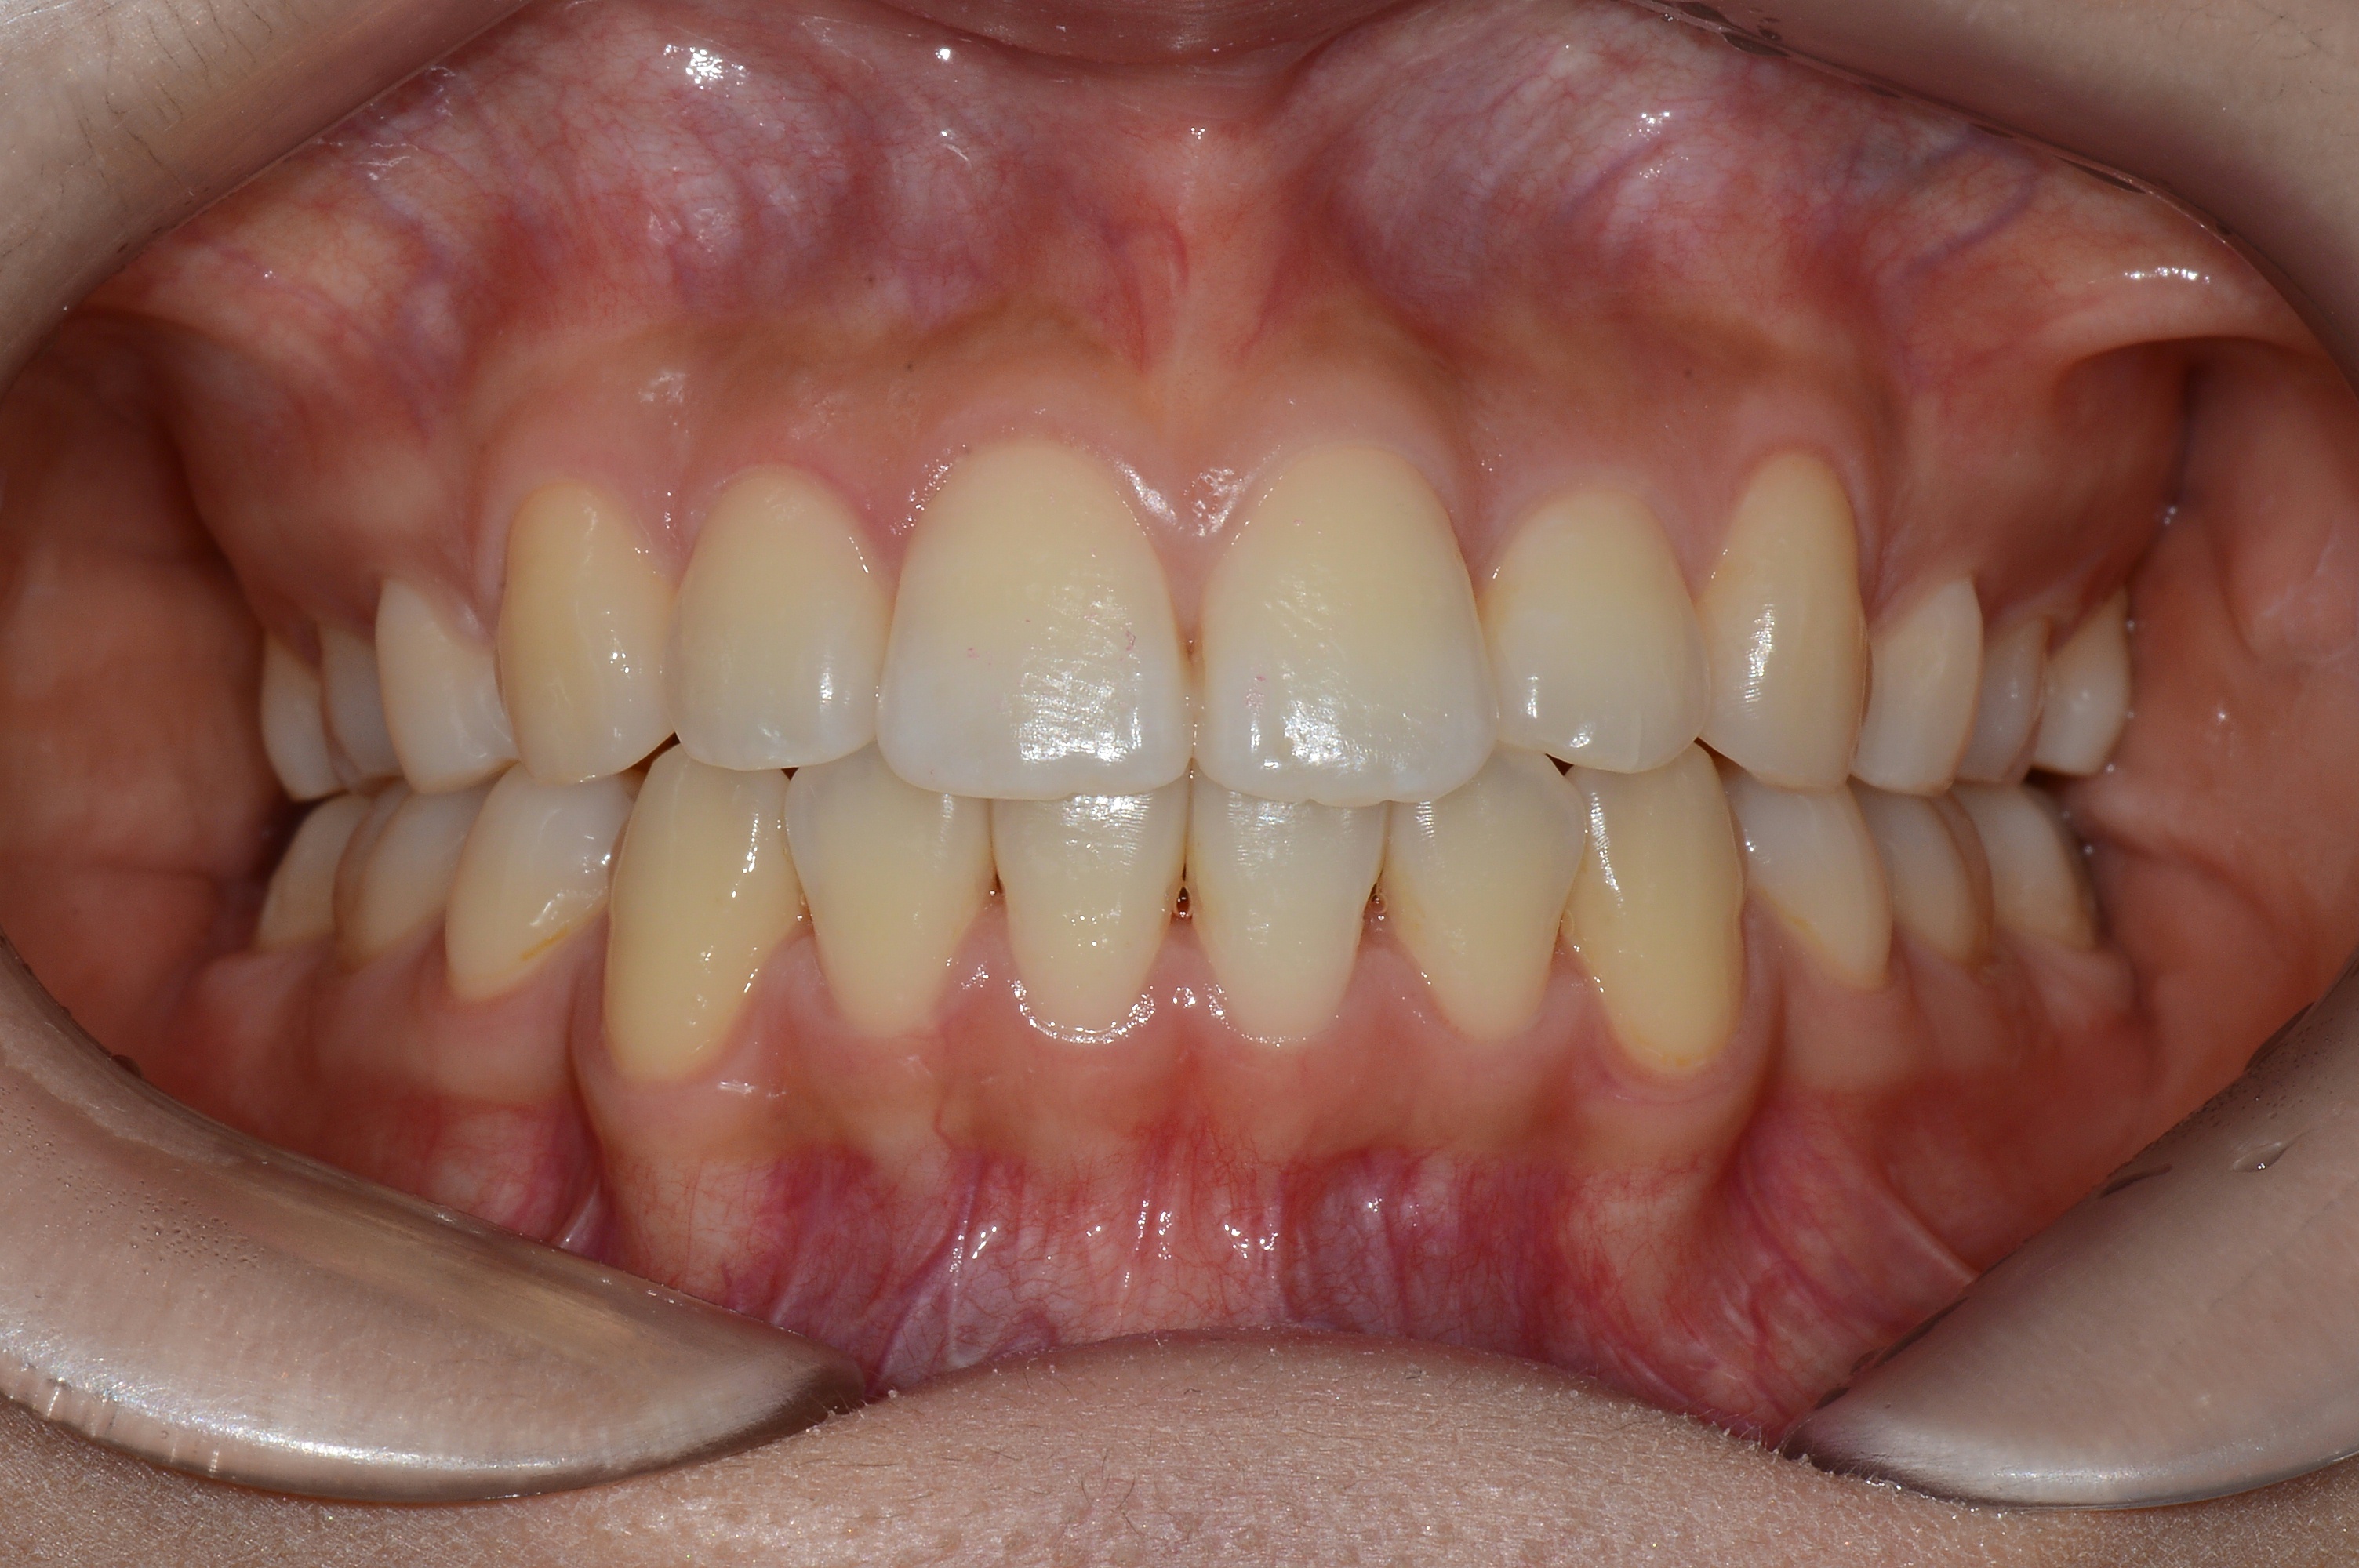

치료 후 사진입니다.